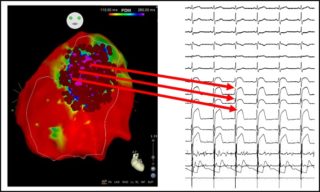

Through the use of dedicated software that is associated with mapping systems, it is possible to reconstruct the three-dimensional geometry of the heart and to identify with precision the areas of myocardium affected by the disease (figure 2).

Once the anomalous electrical substrate has been identified, it is possible to perform the ablation of this area. Radiofrequency disbursements are rapid and precise, in order to limit ablation to only the outer surface of the heart, enabling the elimination of only surface cells (figure 3).

The purpose of the ablation is to eliminate all the anomalous electric potentials located on the epicardium (figure 4), resulting in a complete normalization of the electrocardiogram which no longer shows, after ablation, the classical electrical anomalies of BrS (figure 5). These elements are also associated with the disappearance of malignant ventricular arrhythmias in post-ablation follow-up.